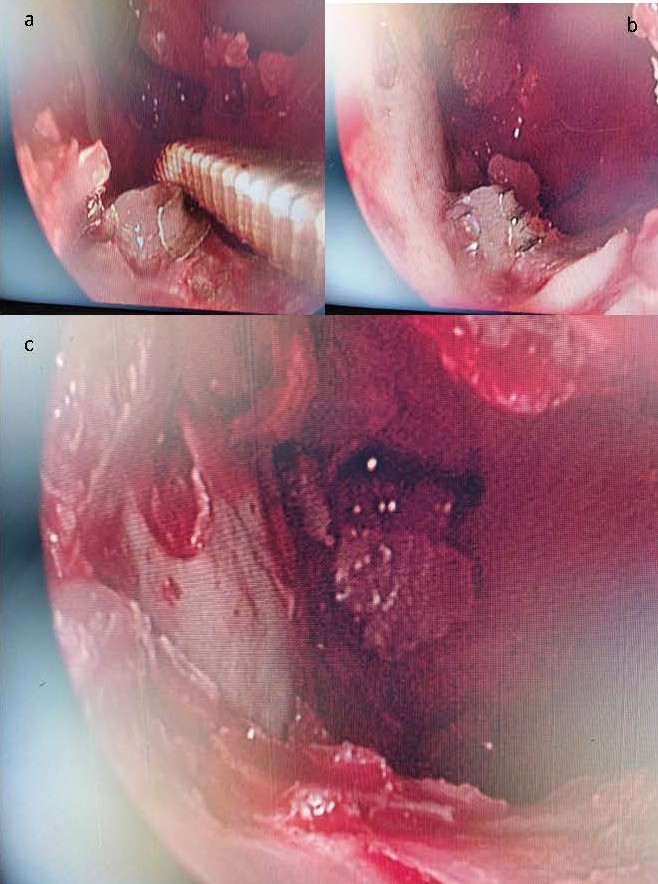

Ethical clearance was obtained from the hospital Ethics Committee and written informed consent from patient for performing the procedure under local anesthesia. Patient was given a choice of general anesthesia, but she preferred local anesthesia after being explained in detail about both local and general anesthesia, as she didn’t wish to undergo intubation and prolonged recovery. After performing FESS, the maxillary sinus was opened using Caldwell-Luc approach (Figure 2) and a 0o endoscope introduced into the maxillary sinus. Titanium screw of the dental implant could be seen arising from the floor of the sinus (Figure 3).

Figure 3. a) and b) 00 endoscopic view of the inside of the left maxillary sinus with instrument pointing to dental implant. c) View after covering implant thoroughly with bone wax.

Mucosa of the sinus was thoroughly debrided. Post-debridement, blood could be seen seeping around the dental implant in the oral cavity, suggestive of oroantral communication around the implant screw. The screw was thoroughly covered with bone wax (0.5–1 cubic centimetres approx.) all around its circumference and antibiotic-soaked gauze pack was placed in the sinus and left nasal cavity. Patient was given ice-packs to place on her cheek to prevent post-operative swelling. Packing was removed after 48 hours and patient was instructed to avoid brushing and chewing on that side for at least 3 weeks. The type of dental implant is shown in Figure 4.